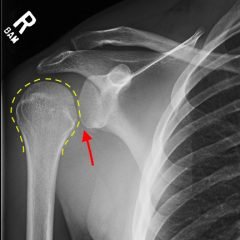

Non-contrast CT of the chest demonstrates hyper-densities within both central and sub-segmental pulmonary arteries bilaterally (see yellow arrows). The right ventricle is dilated.

The diagnosis of pulmonary embolism is usually made by visualizing intravenous contrast filling defects within the pulmonary arteries on CT angiography of the chest. Ventilation perfusion scanning is an alternative modality, but was not available in this case. A hyper-dense lumen sign on non-contrast chest CT1 can identify pulmonary emboli with a reported sensitivity of 36%.2

Utilizing non-contrasted CT of the chest to identify hemodynamically significant central thrombi when IV contrast is not an option may allow for initiation of therapy in a timely manner or may help identify PE when it may not be the primary consideration.